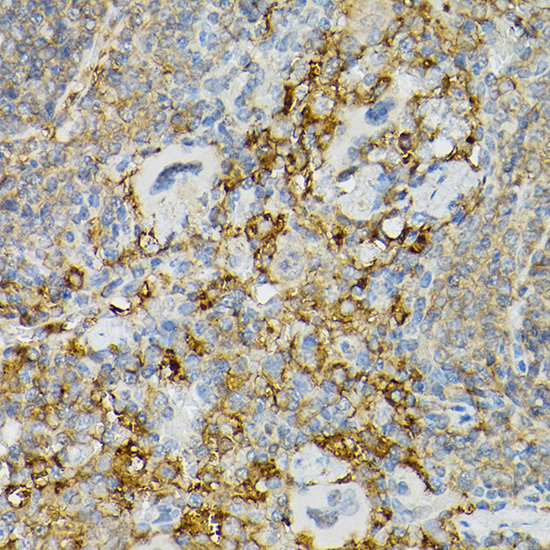

Immunohistochemistry of paraffin-embedded human gastric cancer using CD117/c-Kit antibody.

Immunohistochemistry of paraffin-embedded mouse intestin using CD117/c-Kit antibody.

Immunohistochemistry of paraffin-embedded mouse spleen using CD117/c-Kit antibody.

Immunohistochemistry of paraffin-embedded rat kidney using CD117/c-Kit antibody.

Immunohistochemistry of paraffin-embedded rat intestine using CD117/c-Kit antibody.